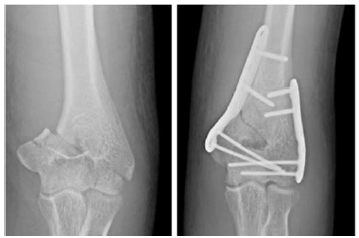

Um paciente de 30 anos de idade foi vítima de queda de árvore há cerca de um dia, sofrendo trauma no cotovelo esquerdo. Foi atendido no pronto-socorro e solicitadas as radiografias retratadas nas figuras.

De acordo com a classificação AO, trata-se de uma fratura